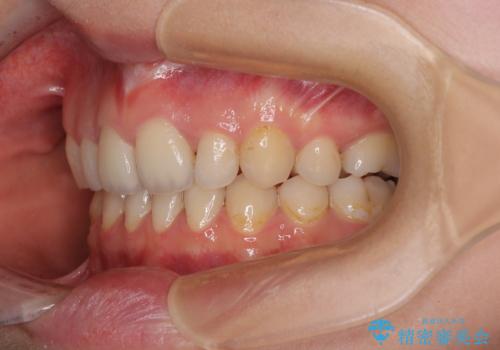

- 後続永久歯の欠損によるスペースと残存乳歯、深い咬み合わせを気にして来院された患者様です。

乳歯を残し、欠損部位のスペースを適正な幅に拡大し、インプラント補綴治療により歯列を整える治療も考えられましたが、ご本人から飛び出している前歯をどうしても引っ込めたいとの要望があったため、残存乳歯ならびに上顎左右第二小臼歯を抜歯して、歯列を整えることとしました。

甚大な咬合力に抵抗して過蓋咬合を改善する必要があり、更には口元が引っ込みすぎることがないように仕上げていく必要もあったため、治療期間は3年を超えましたが、当初計画通りの仕上がりで治療を終えることができました。